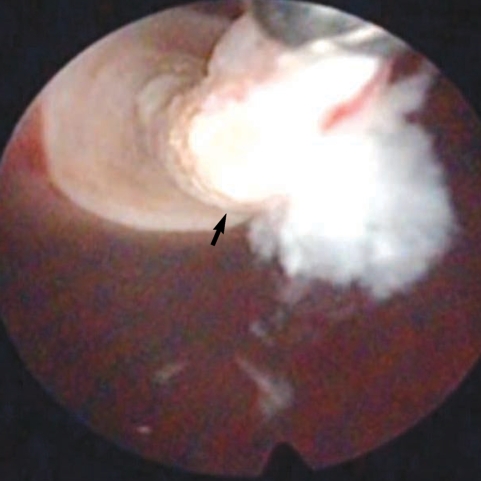

At operation, multiple spargana were found within the mass, around the spermatic cord and scrotal soft tissues (Figs. 1, 2). All identified spargana worms were completely excised. Diagnostic cystoscopy was performed consecutively to evaluate the microscopic hematuria, and a 10-mm sized small nodular mucosal elevation was found in the right side of the dome of the urinary bladder (Fig. 3). Covered mucosa was removed using resectoscope, and a whitish worm-like mass surrounded by granulation tissues was found inside of the nodule (Fig. 4). We tried to remove it by forceps, but it came apart. Histological examinations revealed a foreign body granuloma with a few infiltrates of eosinophils. In a serological test, patient's serum showed a positive reaction to anti-sparganum IgG antibody.